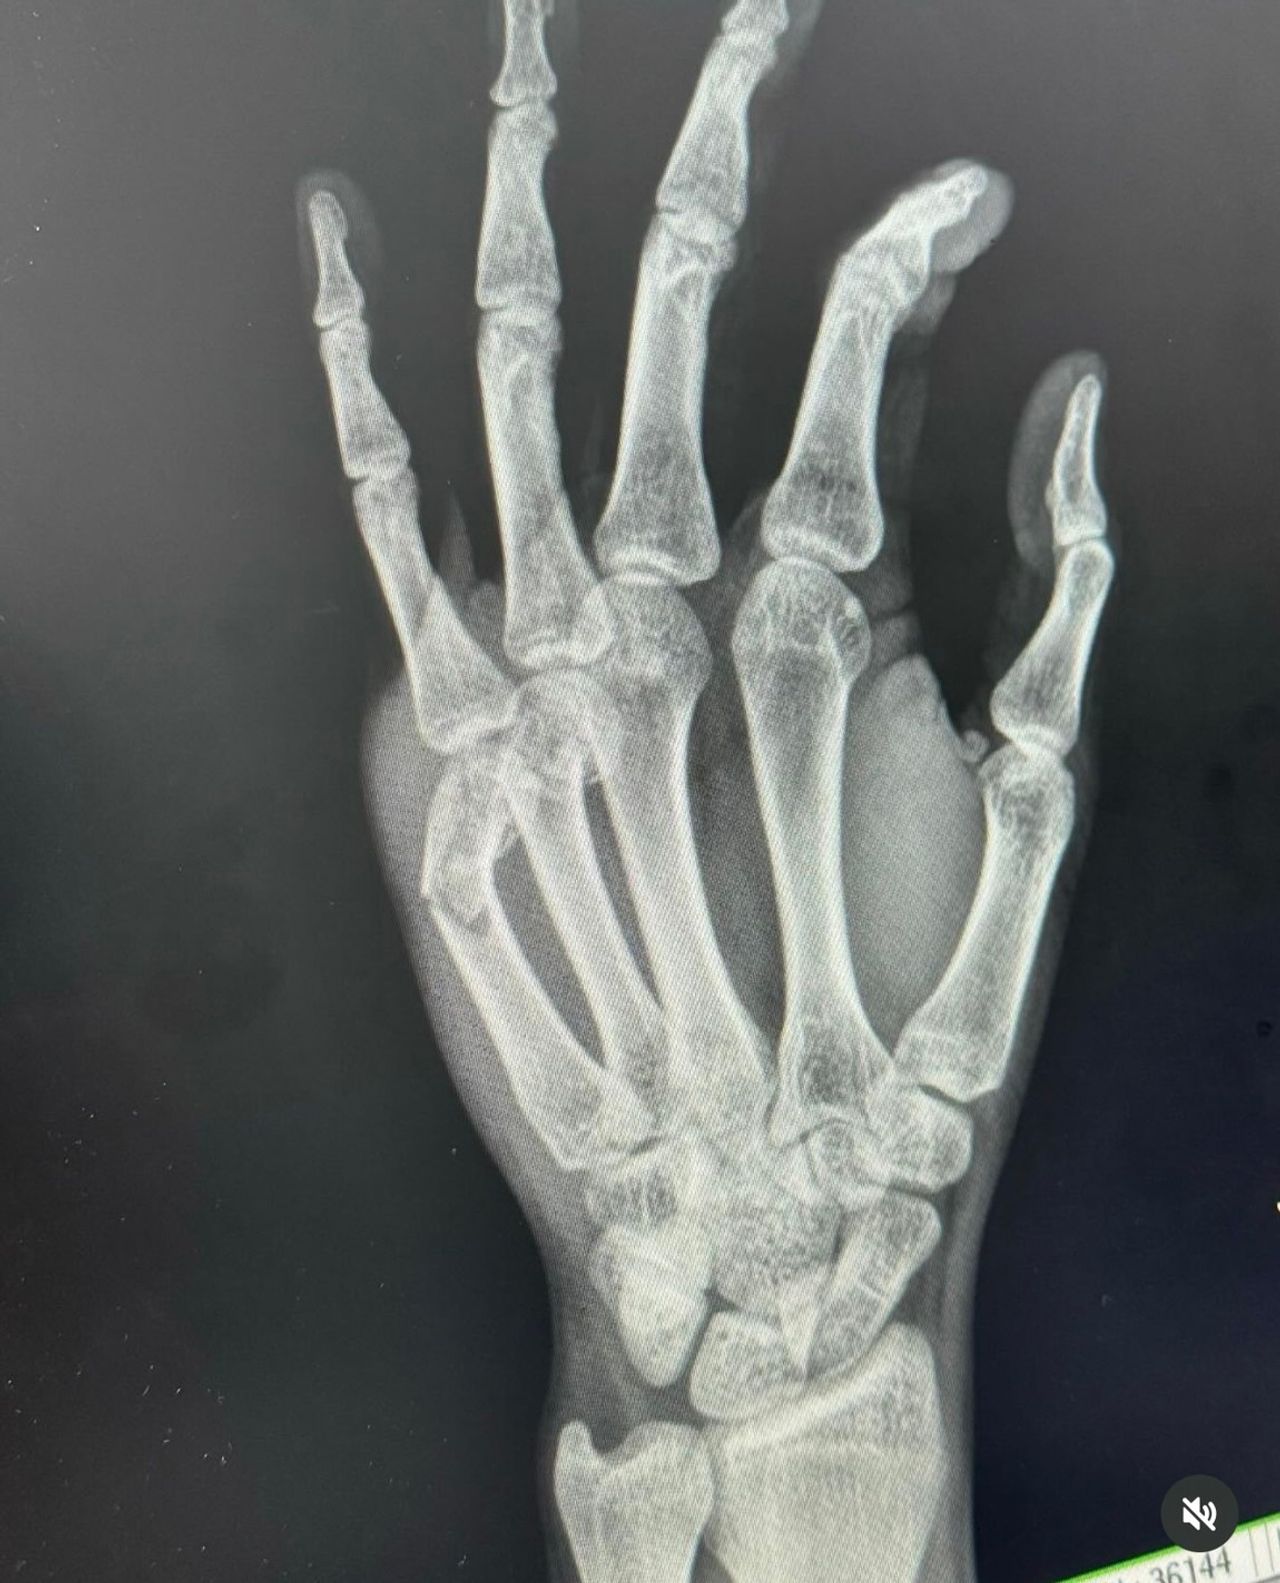

อย่างล่าสุด หนุ่มแชมป์ ได้โพสต์ภาพดามแขน ขณะที่ตัวเองนอนแอดมิตอยู่ที่โรงพยาบาล พร้อมข้อความระบุว่า "เรียกผมว่า แร็ปเปอร์มือหนึ่ง เพราะอีกมือนึง"